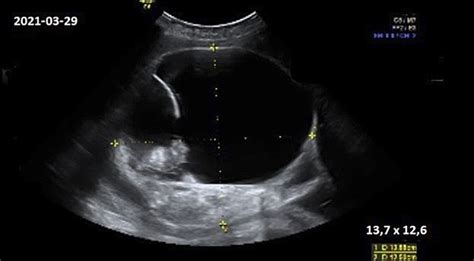

Tai inovatyvus tyrimas, kurio dėka galima matyti ryškų vaisiaus ar kelių vaisių vaizdą. Šio tyrimo metu galima pamatyti savo vaikelio veido bruožus, stebėti, kaip jis žiovauja ar čiulpia nykštį. Tiriant ultragarsu ankstyvoje nėštumo stadijoje atliekamas sprando raukšlės matavimas dėl galimų chromosominių vaisiaus ligų, vėliau matomos smegenų struktūros, stuburo ir kitų vidaus organų vystymasis, nustatomas tikslus vaisiaus dydis, gimdymo data, lytis, 34-35 nėštumo savaitę tiriama fetoplacentinė (tarp vaisiaus ir placentos) virkštelės kraujotaka. Atliekant 3D/4D echoskopiją, taikoma pažangiausia vaisiaus širdutei tirti STIC programa. Taip pat 4D ultragarsinis tyrimas gali 100% tikslumu nustatyti kūdikio lytį, jei tik tyrimo metu mažylis nebus pasislėpęs.

Monitoriuje iš karto rodomas nuskenuotas gimdos vaizdas. Speciali technologija leidžia vaizdą užfiksuoti ir sujungti vaizdus į visumą. Vaizdai sujungiami į trumpą filmuką, kuris leidžia pamatyti kūdikio ar kelių kūdikių judesius. 4D ultragarsinio tyrimo dėka galima išsamiai apžiūrėti vaisiaus veidą bei stebėti kaip mažylis judina galūnes ar bando apsiversti. Taip pat ši šiuolaikiška technologija leidžia tiksliau apžiūrėti vaisiaus anatomines struktūras, diagnozuoti įgimtus vaisiaus vystymosi sutrikimus, smegenų struktūros patologijas. 4D echoskopija skiriasi nuo 3D echoskopijos, kadangi skenuojamas vaisiaus paviršius ir vaizdas iš karto matomas ekrane.

Dažniausiai tyrimas atliekamas tarp 24 ir 34 nėštumo savaičių, o apie 27-28 nėštumo savaitę yra idealiausias laikas, nes kūdikio veido bruožai jau būna susiformavę, kūdikis būna užsiauginęs šiek tiek riebalinio sluoksnio ir dar turi pakankamai vietos judėti. Nerekomendotina tyrimą nukelti į nėštumo pabaigą, nes mažylis susilenkia ir tuomet tampa sunkiau pamatyti jo ar jos veido bruožus.